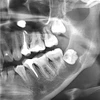

التهاب ما حول الغرسات السنية

التهاب الغشاء المخاطي حول الغرسة

علاج الزرع السني